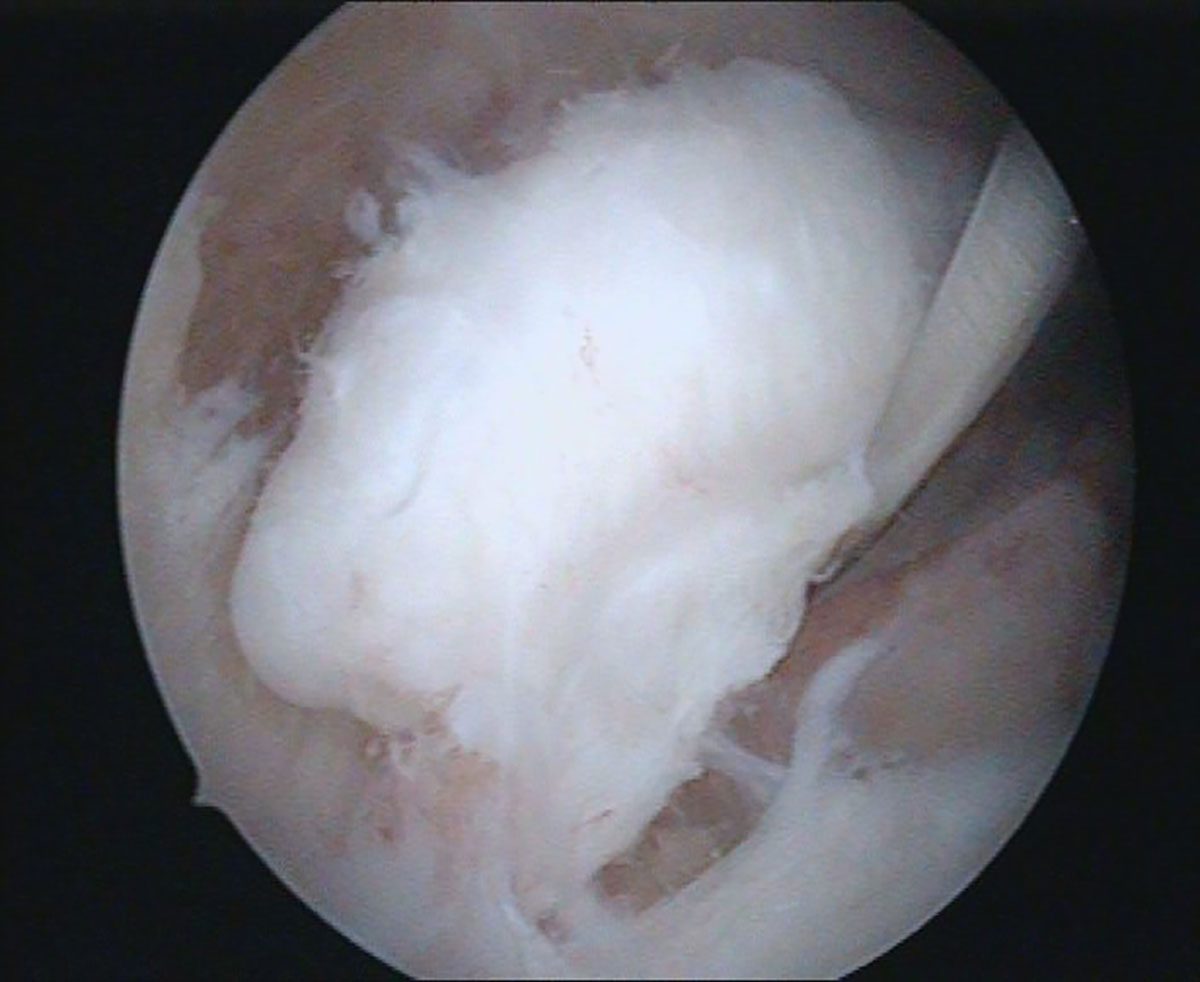

Vor allem die Entfernung freier Gelenkkörper ist eine Domäne der arthroskopischen Behandlung (Abb. 4). Auch Ellenbogensteifen lassen sich je nach Schweregrad erfolgsversprechend arthroskopisch therapieren [9,14] (Abb. 5).